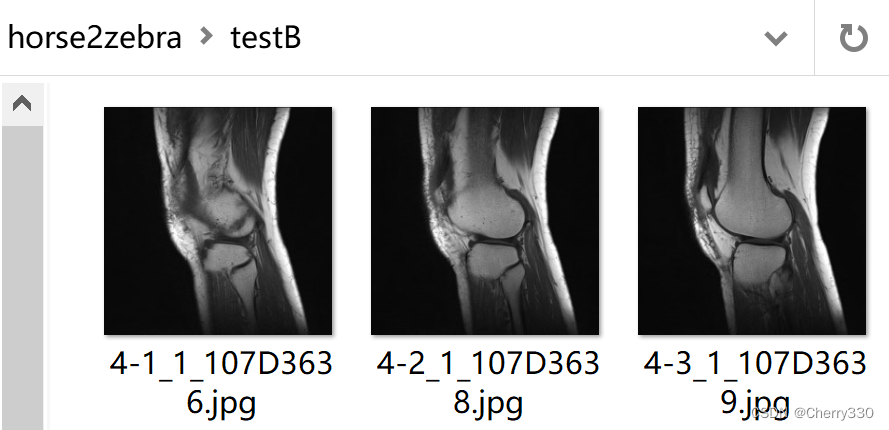

需要注意的是,trainA和trainB是训练的数据集,testA和testB是测试的数据集,大家记得按照自己需求进行分配哦~ trainA和testA是需要转换的图片,就是我做的这个的T2图片,trainB和testB是风格图片,就是我的任务中的T1图片。如图5。

图5 数据集构成